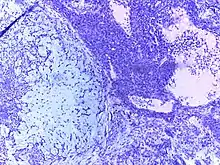

![]() | Follicular lymphoma | Micrograph showing a small B-cell lymphoma compatible with follicular lymphoma. H&E stain. | Category: Histopathology of follicular lymphoma | Follicular lymphoma |